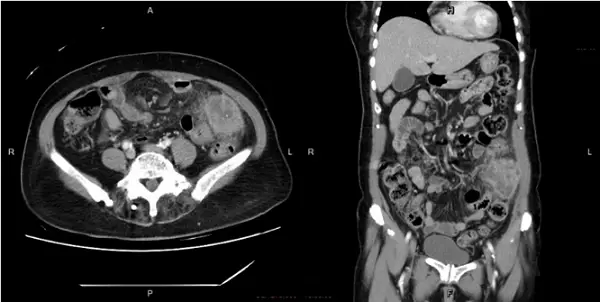

電腦斷層橫斷面與冠狀位皆可見:

- 乙狀結腸位置有明顯壁增厚,且周邊脂肪組織呈模糊混濁(fat stranding),顯示局部發炎反應。

- 結腸外有一大小約4-5 cm的低密度液體病灶,壁緣強化且內含氣泡,看似膿瘍形成。

- 未見明顯閉鎖性氣腸(no obstruction pattern),也無腸管壁氣腫或門脈氣體(排除腸缺血指標)。

- 膿瘍位置緊鄰左下腹乙狀結腸區,符合局限性腹膜炎表現。

這些CT所見符合「pericolic abscess」:周邊有wall-enhancing fluid collection with gas within or adjacent to the inflamed colon (pmc.ncbi.nlm.nih.gov)。